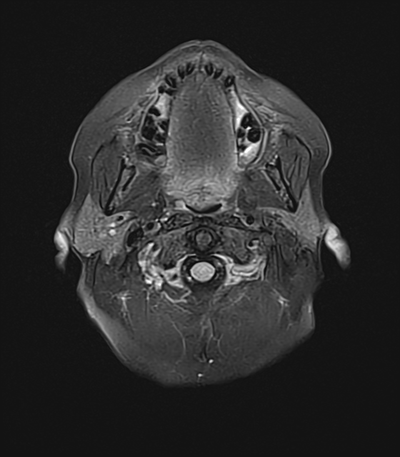

An 50 year-old man with lung adenoCA (known metastases to brain, spine, and adrenal glands) presents to the ED with worsening right arm and leg weakness. He had just gotten a routine MRI of his brain yesterday that re-demonstrated his known right occipital and left frontal metastases, though with an increase in vasogenic edema (mainly associated with the left frontal metastasis) as compared with prior. The ED consults you because of his abnormal MRI with worsening symptoms, and to inquire whether surgical intervention is acutely warranted.

MRI brain (FLAIR)